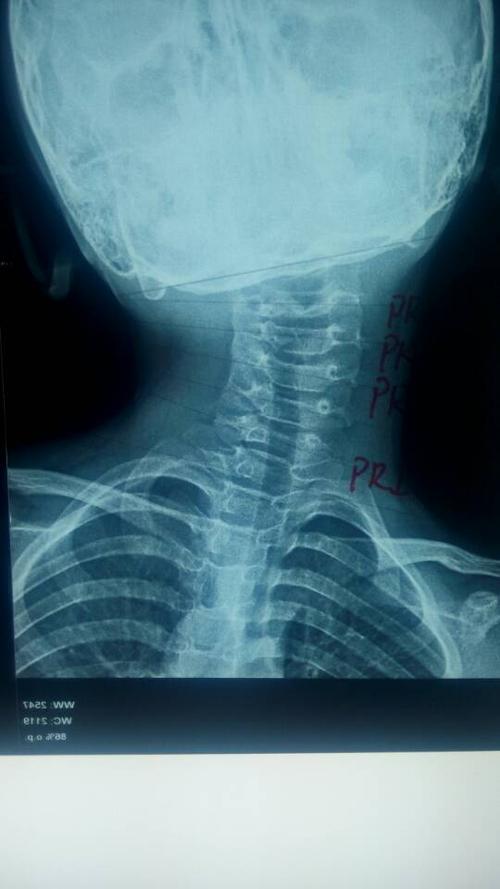

颈部x线正位片显示颈椎小关节紊乱,颈椎明显侧弯.

颈椎侧弯脖子

颈椎侧弯脖子,护脖子颈椎护颈椎套